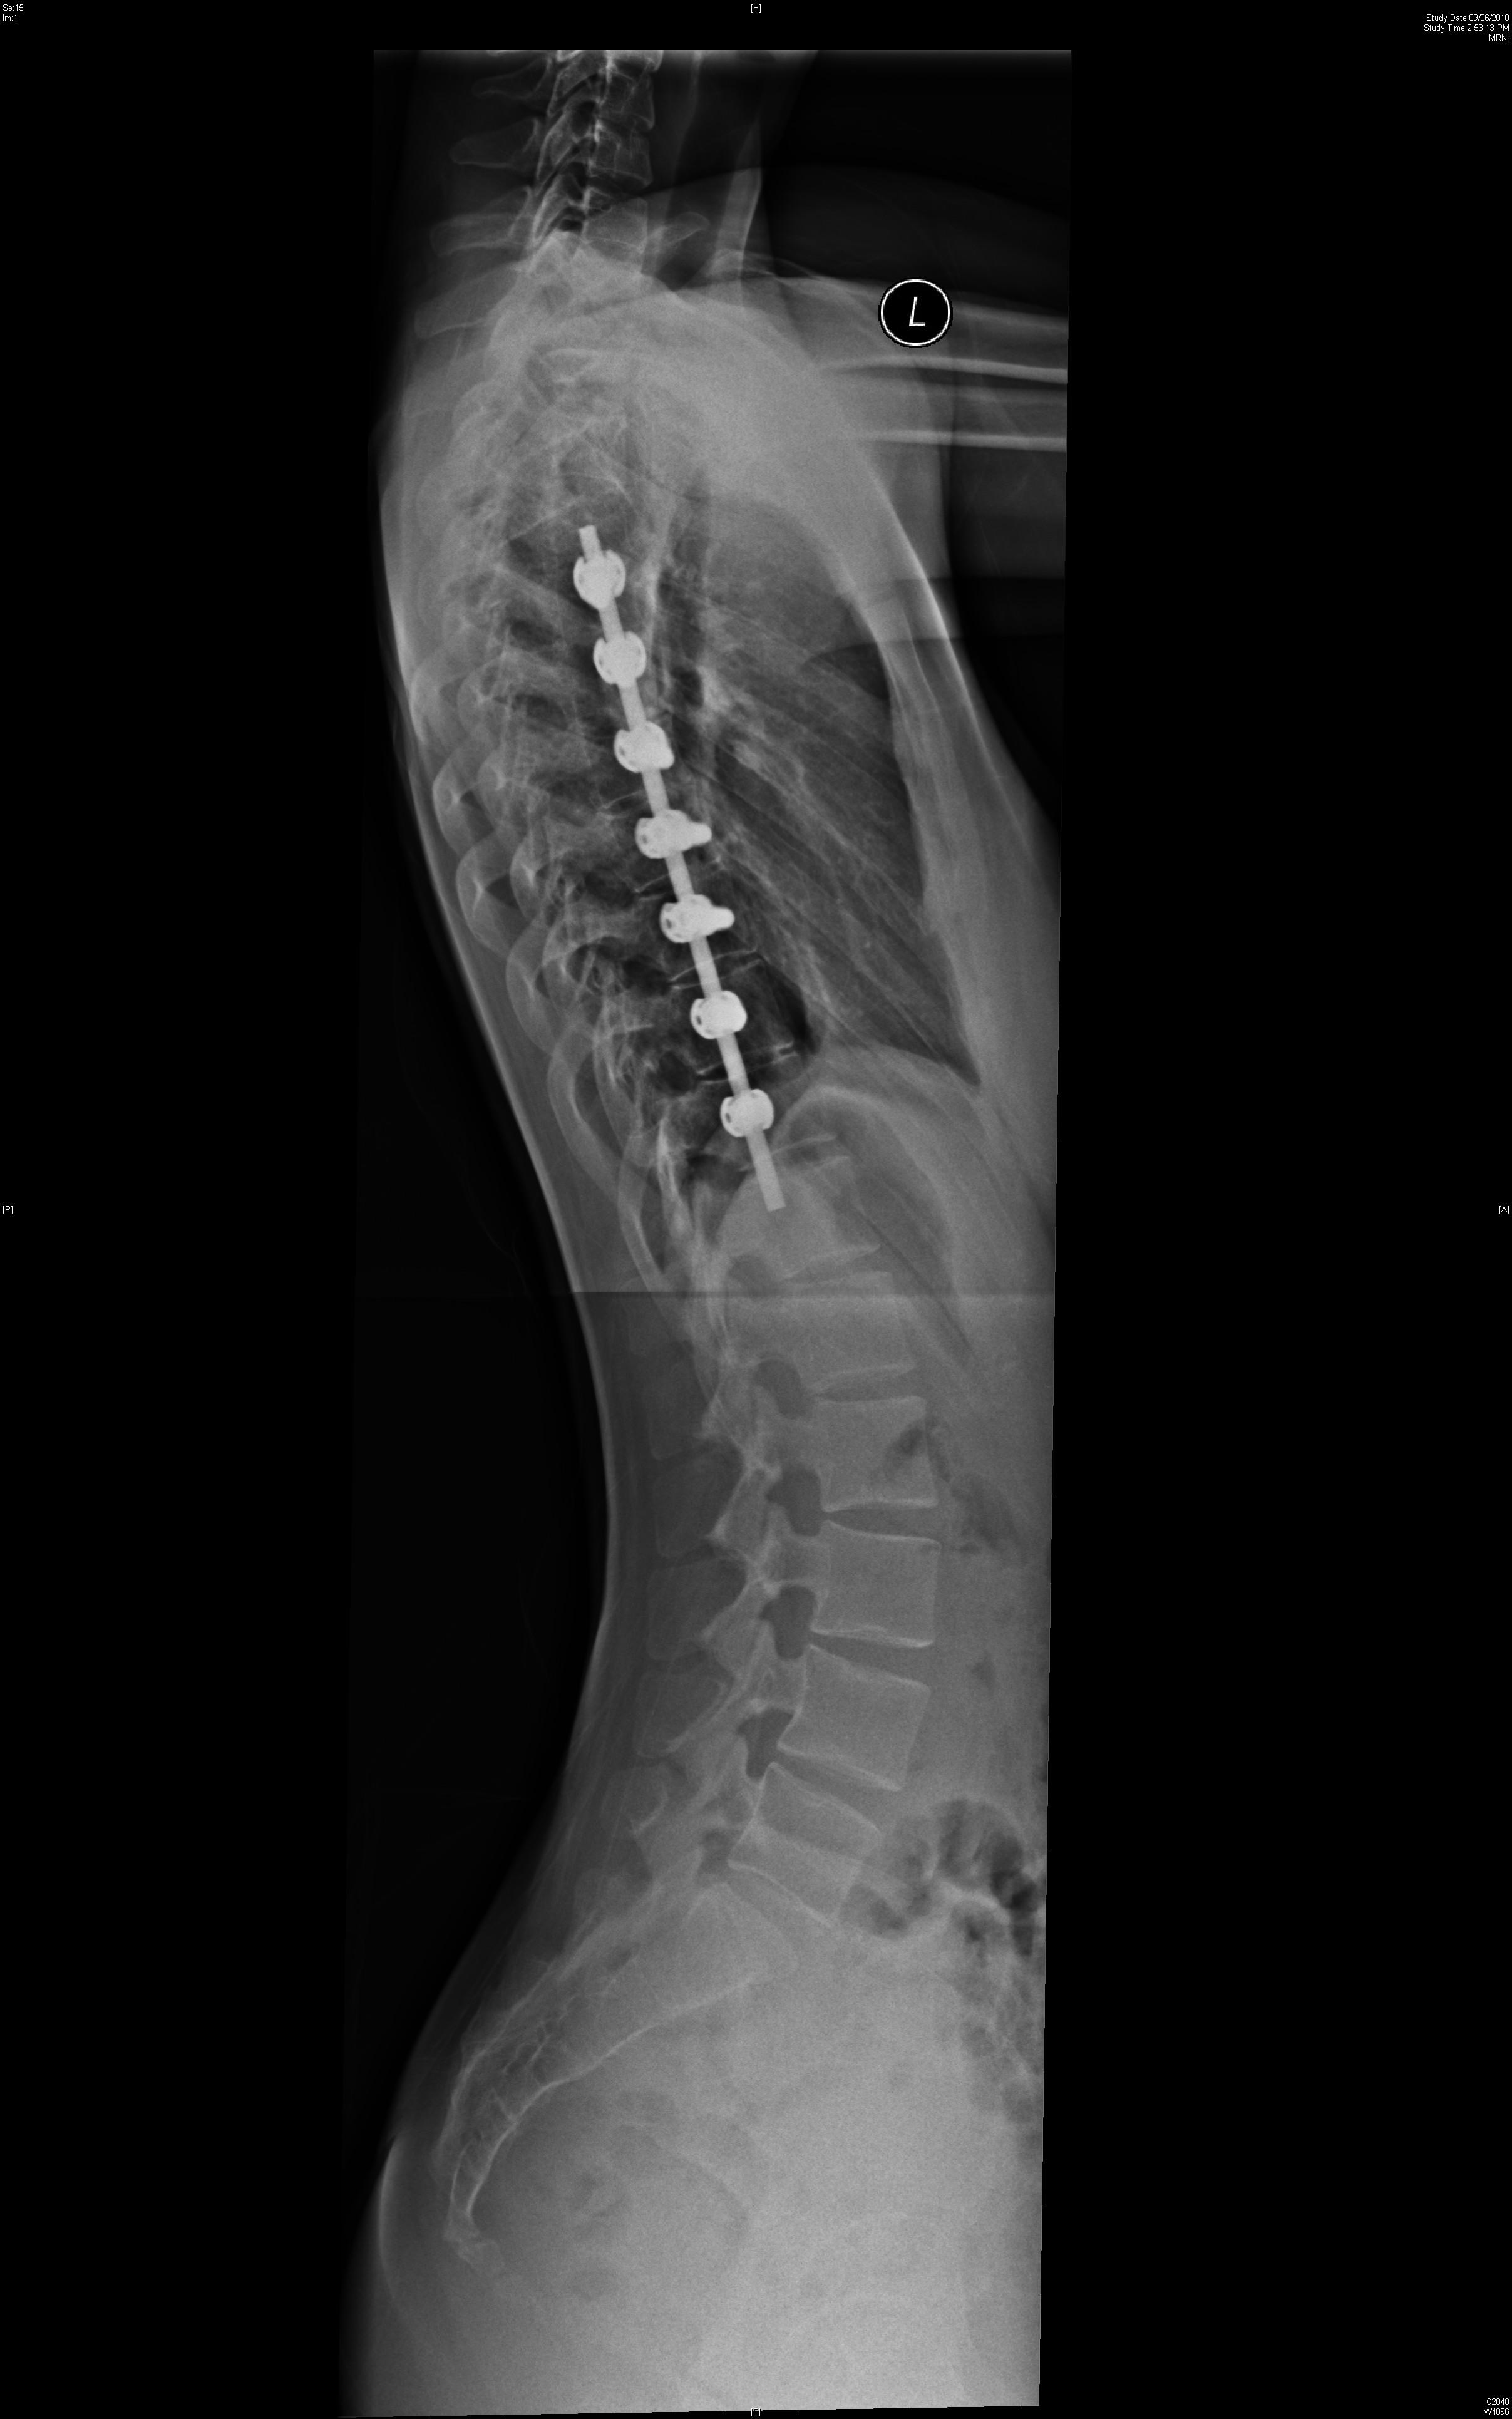

Currently artificial disc replacement can be used for the lumbar or the cervical spine. Many different models have been developed. The majority consists of two metal plates that have teeth to anchor the implant onto the bone of the vertebral bodies. Between the two plates is a metal core or a plastic core made up of polyethylene that allows for motion. Figure 1 shows a lumbar artificial disc replacement. Figure 2 shows a cervical artificial disc replacement.

The technique to insert an artificial disc (whether in the neck or low back) is routine and safe. For the cervical spine it involves going from the front of the neck. For the lumbar spine, it involves going through the abdomen. The procedure begins by removing the gelatinous disc between the vertebrae. Once the disc is removed, two metal plates are pressed into the bony endplates above and below the space now vacated by the disc. Metal spikes hold these plates in place on the bone. Eventually bone will grow over and around the metal plates. In between the metal plates is a metal or plastic core made of a polyethylene. Figure 3 shows the artificial disc placed in the spine.